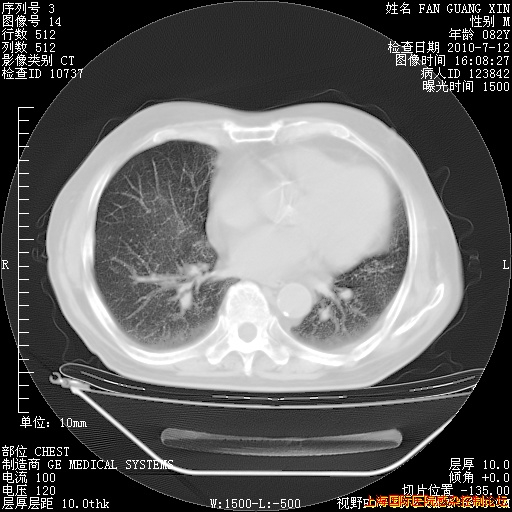

6月12日纵膈窗

整整相隔30天的肺部CT好像有所好转啊。甲强龙减量第3天,需要观察体温。

海管,自昨日你和我通完话后,不知您岳父消化道症状有无缓解?体温怎样?阅读7.12日胸部ct,个人认为目前激素治疗是有效的,甲强龙减量是适宜的。因在抗痨治疗,需密切观察肝功、肾功能和血常规。不过,老年、长期住院和大量使用激素,很担心菌群失调发生